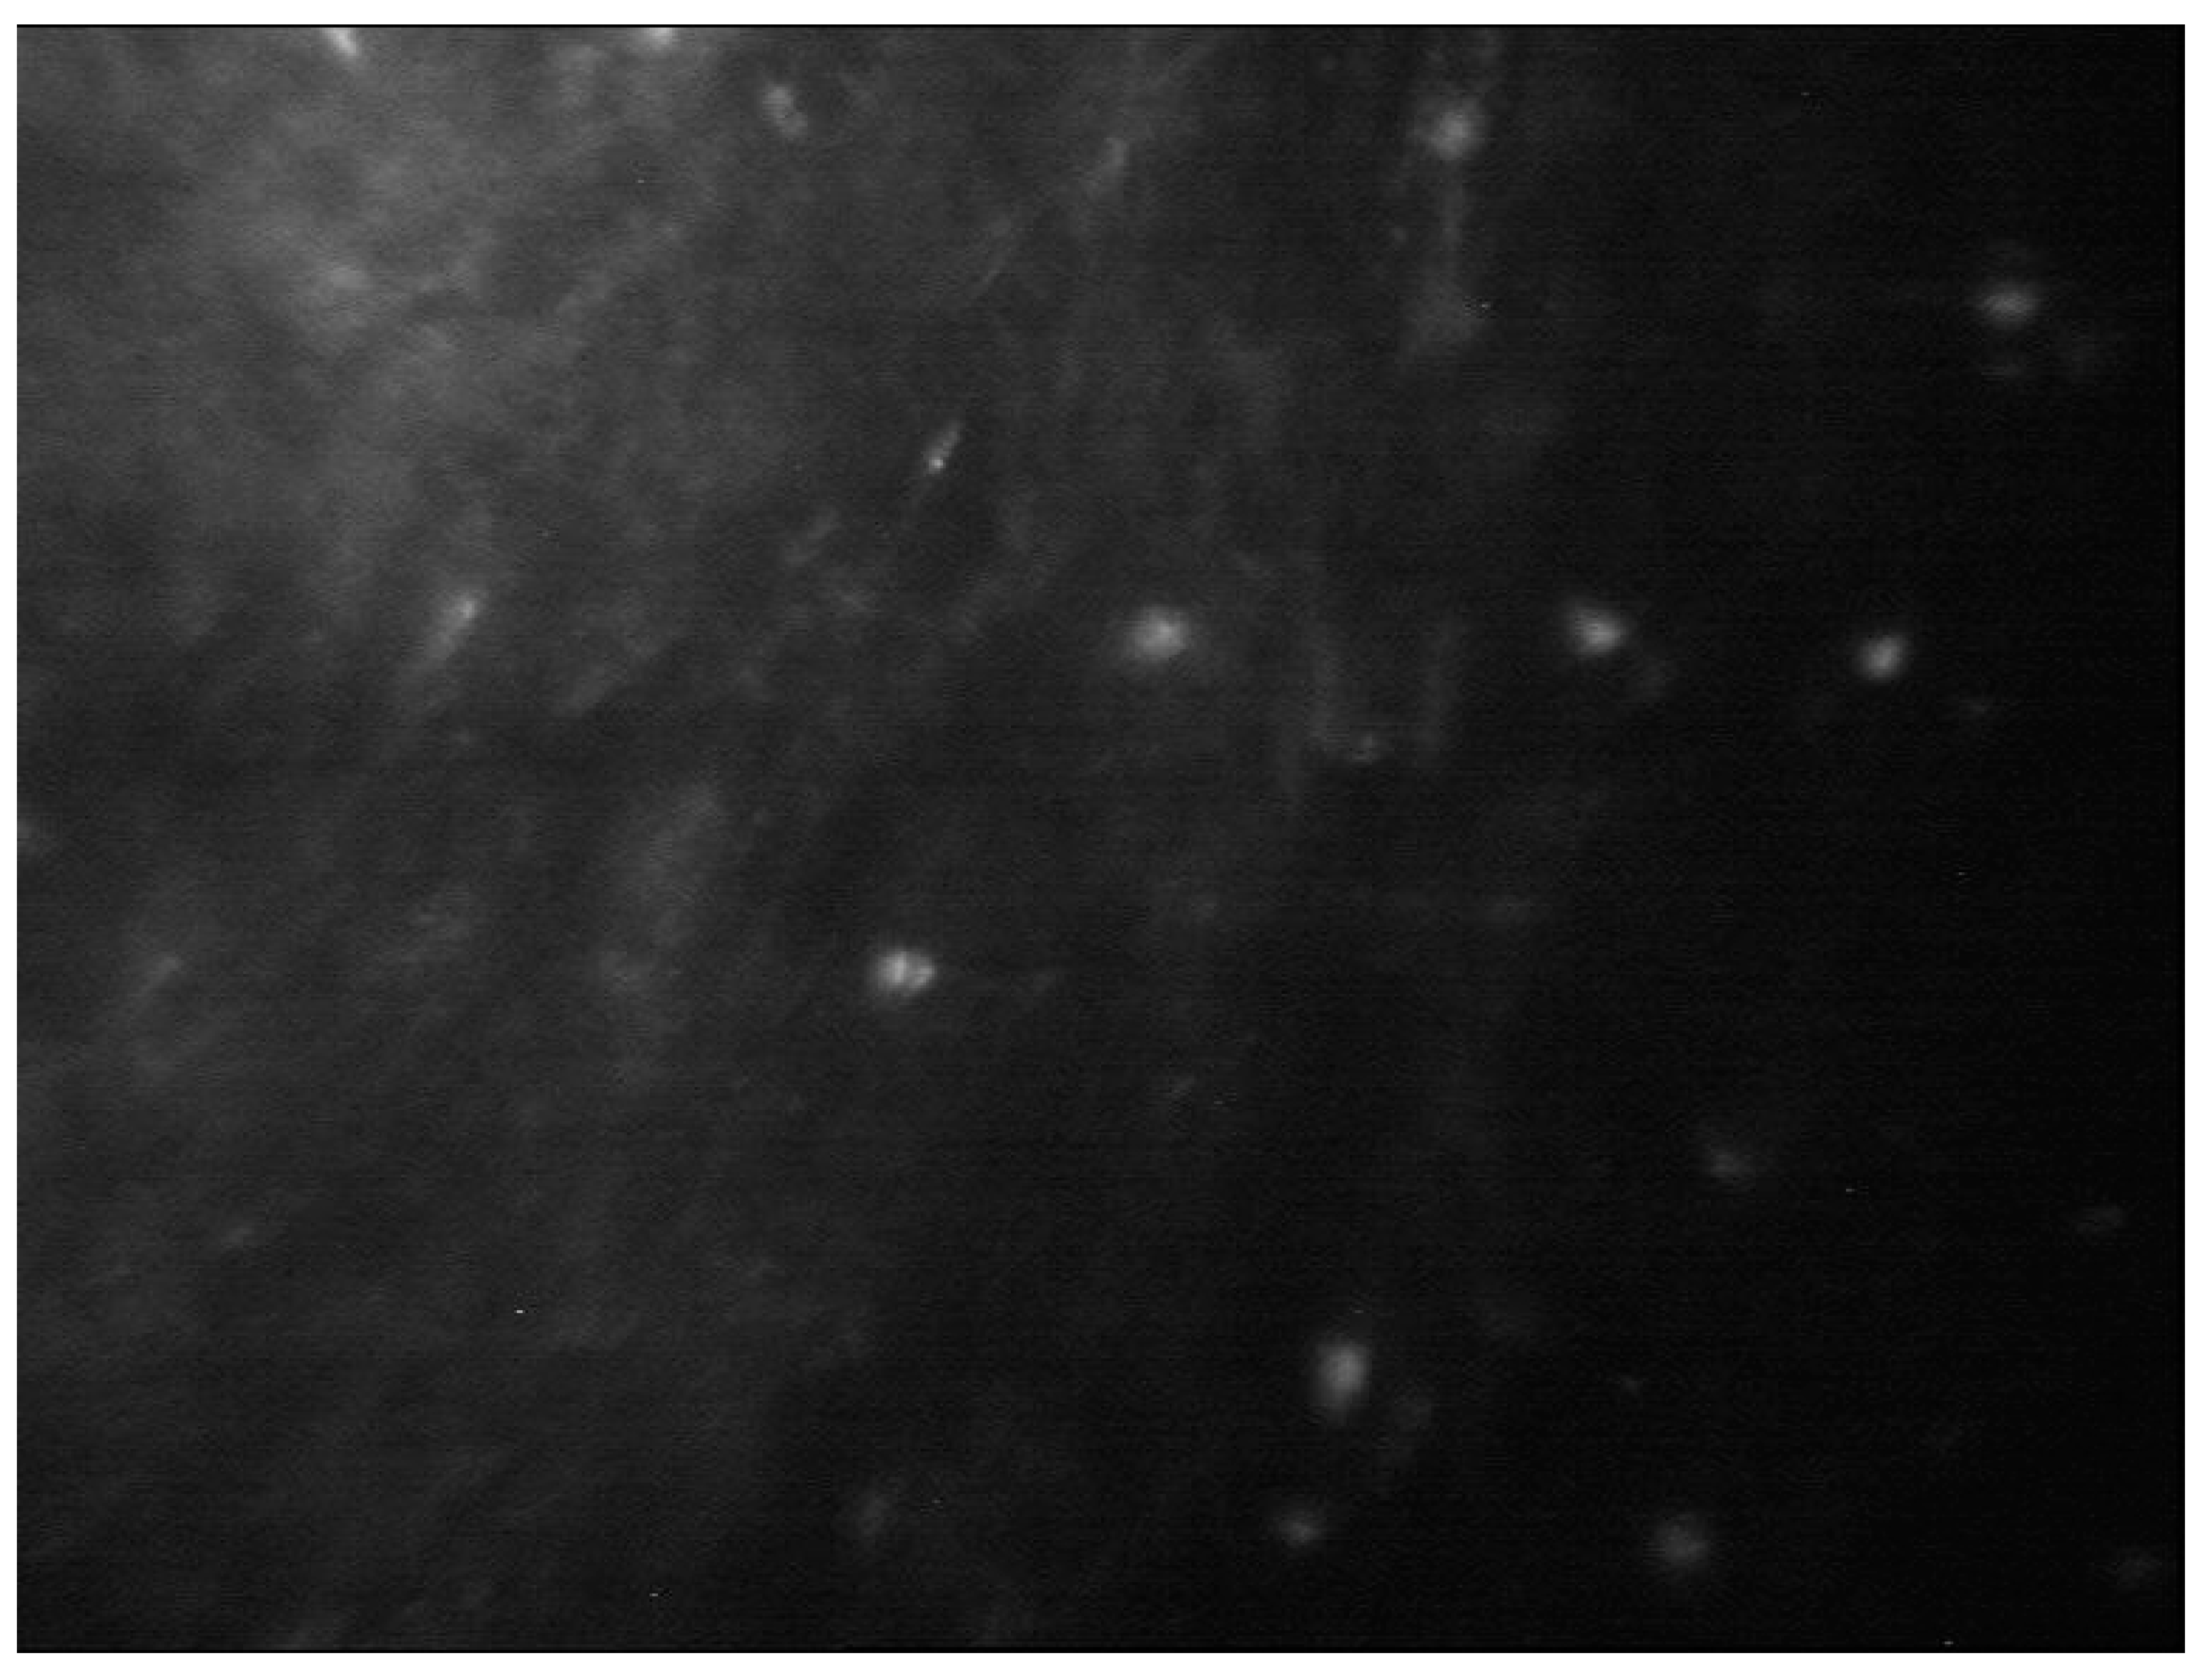

IVCM is a key diagnostic test in AK with an overall sensitivity of 80-100% and specificity of 84-100% [11,34,35,36,37,38] Acanthamoeba spp. can present as cysts or trophozoites. Cysts (dormant form) appear as hyperreflective, spherical and well-defined double-wall structures of ~ 15-30 µm in diameter in the epithelium or stroma. Trophozoites (active form) appear as hyper-reflective structures of 25-40 µm which are difficult to discriminate from leukocytes and keratocyte nuclei. [4,11,39]. Acanthamoeba spp. can also present as bright spots, signet rings and perineural infiltrates. Perineural infiltrates are a pathognomonic characteristic of AK which appears a reflective patchy lesions with surrounding hyper-reflective soindle-shaped materials [11] (Figure 7).

Figure 7. In vivo confocal microscopy of Acanthamoeba keratitis.